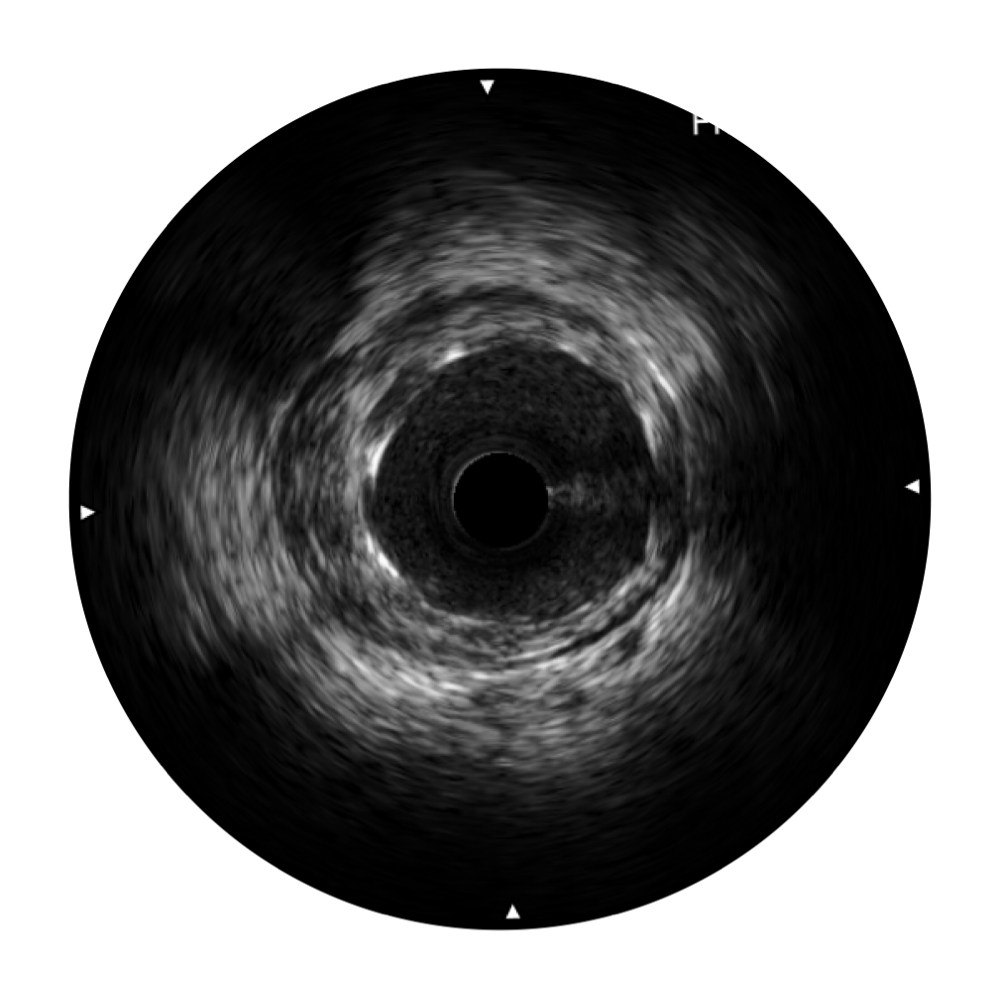

传统IVUS图像

对比传统IVUS导管成像,MILE米乐集团官网宽频IVUS图像的近场支架梁显影更细腻,远场中膜外血管仍清晰可辨,兼顾远中近,兼顾分辨力与穿透深度